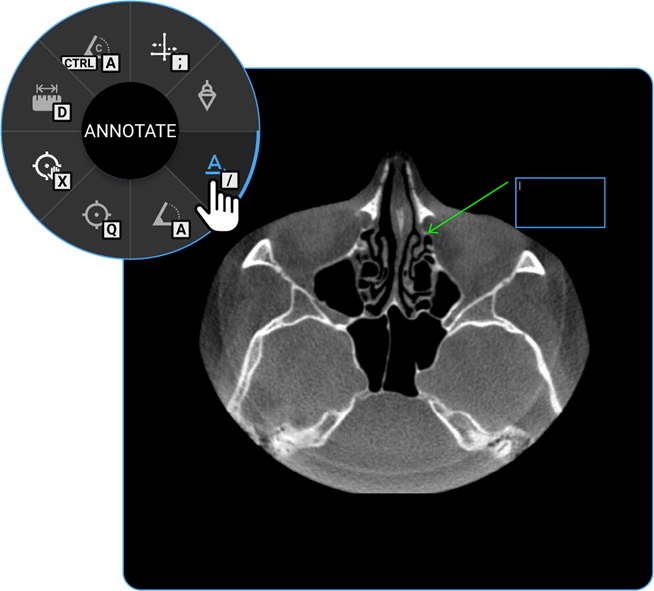

- Annotate: Use the Annotate tool to add text or markers to the image for documentation or instructional purposes.